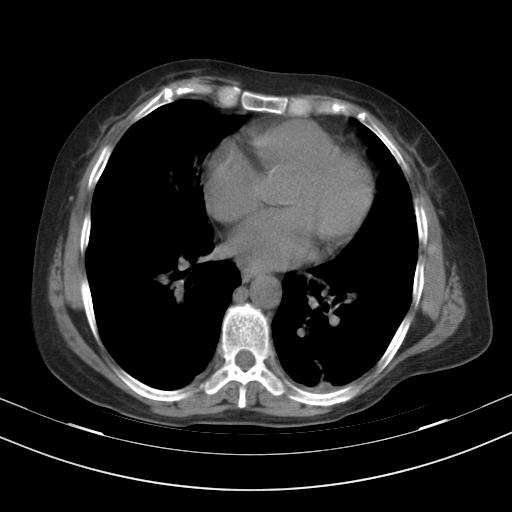

老年女性,嗜睡3天,意识模糊。轻咳,无发热。

1)两肺感染性病变;建议抗炎治疗后复查。2)纵隔淋巴结肿大。3)左侧胸腔积液。

1)先考虑两肺感染性病变;建议抗炎治疗后复查。

2)纵隔淋巴结肿大。

3)左侧胸腔积液。